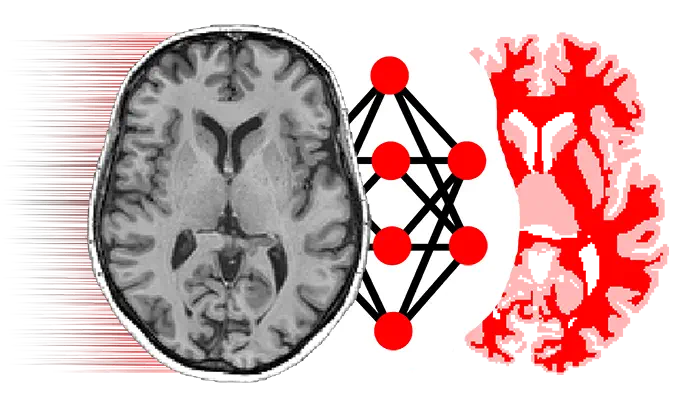

NiftyNet: Open-source convolutional neural networks platform for research in medical image analysis and image-guided therapy Jan 1, 2020 Go to Project Site NiftyNet logo Old Tom Vercauteren Professor of Interventional Image Computing Tom’s research interests include machine learning and computer assisted interventions